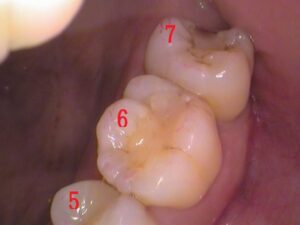

奥歯の歯の3本です。

5番目、6番目、7番目の歯があります。

よく見てみると、

青枠の箇所に「レジン」というプラスティックの合成樹脂が詰められてあります。

白い材料なので一見分かりにくいですが、経年劣化による変色もあり、継ぎはぎみたいに歯に埋められています。

レントゲン(エックス線)検査で治療前に確認済みですが、このレジンの中で虫歯があります。